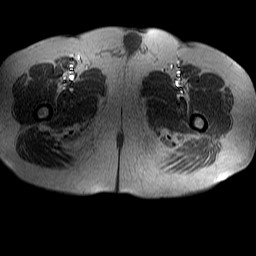

Esami: RMN BACINO

Evidenti e simmetriche alterazioni osteofitosiche in regione coxo femorale con riduzione delle rime articolari. Degenerazione completa del cercine glenoideo. Non attuali segni di versamento articolare. Non segni di edema osseo che escludono attuale algodistrofia od osteonecrosi. Lieve e simmetrica riduzione del trofismo della muscolatura glutea.